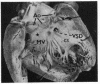

The clinical and anatomical findings in two patients with isolated ventricular inversion and situs solitus are described. The other 4 previously published cases are reviewed. The 6 patients with this malformation, all without pulmonary stenosis, presented a clinical picture of cyanotic congenital heart disease, associated with increased pulmonary blood flow (hypoxaemia and cardiac failure). The importance of different diagnostic tests is discussed and it is concluded that angiocardiography is the only definitive means of establishing the dianosis. Because the physiopathological disturbance is the same as in transposition of the great arteries, both malformations should be similarly considered with respect to diagnosis and treatment. Nevertheless, the high incidence of certain associated malformations in cases of isolated ventricular inversion adds to difficulty in diagnosis, and makes a good result from the Mustard procedure less likely than in transposition of the great arteries.